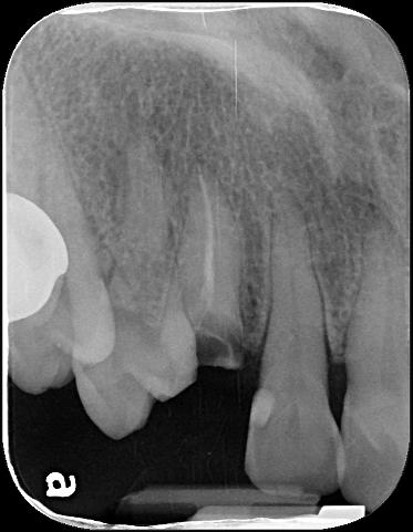

本病患為嚴重蛀牙,導致牙齒斷裂,經評估,骨頭良好,因此可拔牙後立即植牙,減少等待時間,待植體癒合後,再進行膺復處置

治療前,牙齒斷裂

治療前,牙齒嚴重斷裂